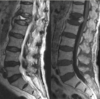

Differentiate the 3 types of MRI